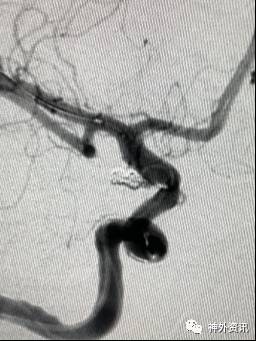

病例一

病例二

病例三